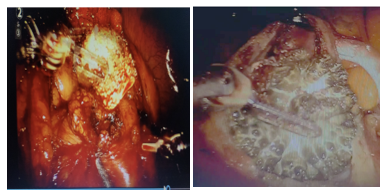

Intraoperatively we first performed cystoscopy for RGP and stenting but owing to the presence of severe mucosal edema we could not find the bilateral ureteric orifice. Therefore, the decision of robotic-assisted laparoscopic pyelolithotomy and cystolithotomy was made. The kidney was intraoperatively located with intraoperative ultrasound, retroperitoneal dissection was performed, pyelolithotomy was performed, the stones were removed with the needle holder. The bladder was dissected, a horizontal incision was made over the bladder, and cystolithotomy was performed followed by bladder stone removal. Then, retrograde DJ stenting was performed with an extensive search for the bilateral ureteric orifice. Robotic assisted pyeloplasty and bladder reconstruction were performed after bladder washing. We placed 22 fr abdominal drains in the left lumbar region with a 16 fr Foley’s catheter. (Figure 3).

Figure 3:- Intraoperative images showing robotic pyelolithotomy with cystolithotomy